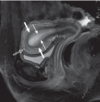

Q.Qué estructura se encuentra comprometida y qué grado lesión asignarías.

LCA, grado II.